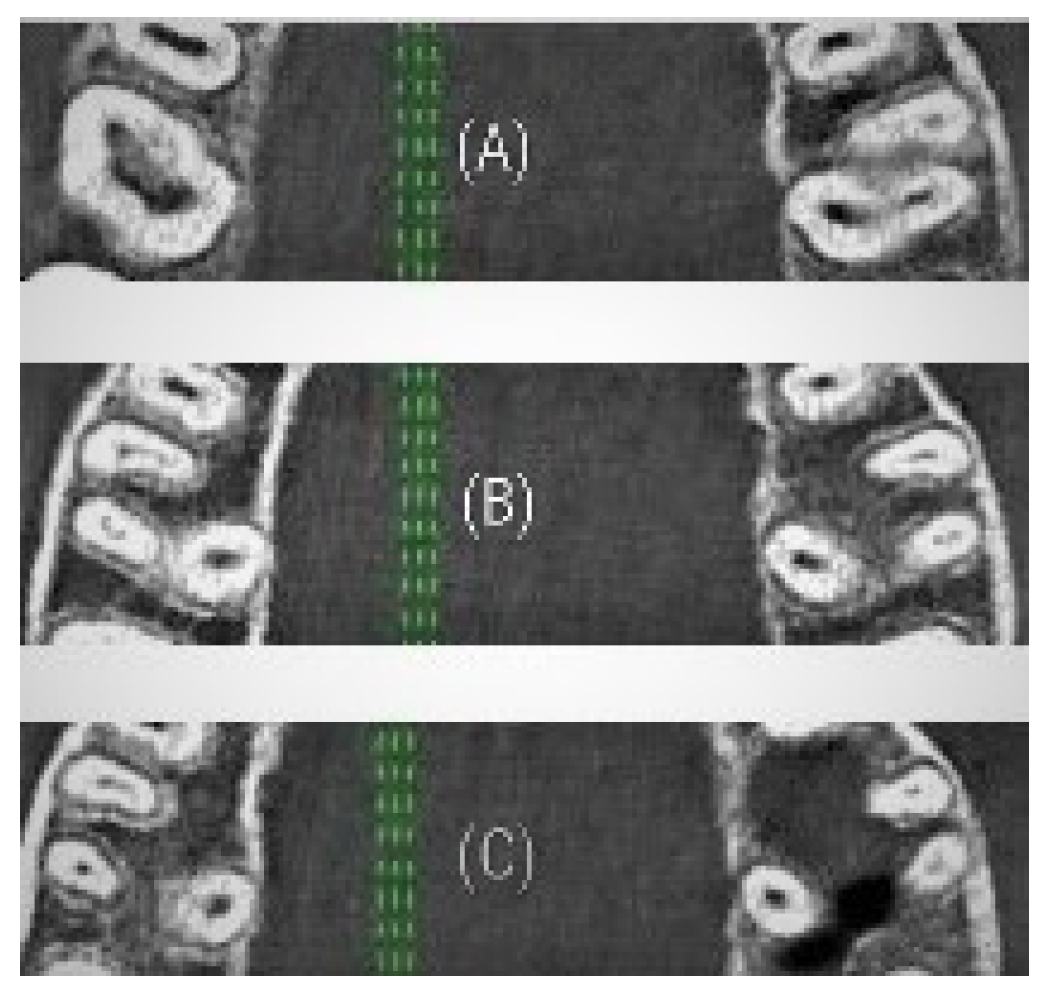

| Type I | Un-changed cross-sectional root canal shape from coronal to apical third |

| Type II | Changed cross-sectional root canal shape in the middle third |

| Type III | Changed cross-sectional root canal shape in the middle and apical thirds |

| Type IV | Changed cross-sectional root canal shape in the apical third |